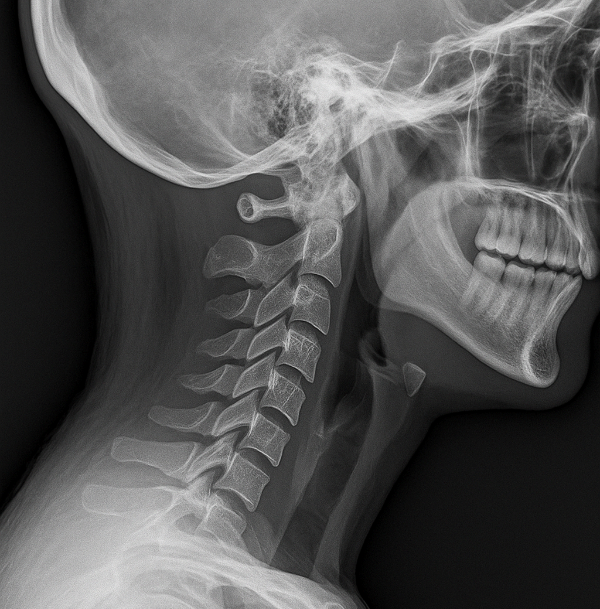

๋ชฉ๋์คํฌ(๊ฒฝ์ถ ์ถ๊ฐํ ํ์ถ์ฆ)๋ ๋ชฉ๋ผ ์ฌ์ด์ ๋์คํฌ๊ฐ ํ์ด๋์ ์ ๊ฒฝ์ ์๋ฐํ๋ ์งํ์

๋๋ค.

๋ํ์ ์ธ ์ฆ์์ ๋ค์๊ณผ ๊ฐ์ต๋๋ค:

- ๋ชฉ์ ๋๋ฆด ๋ ๋ปฃ๋ปฃํ๊ฑฐ๋ ํต์ฆ์ด ์ฌํ๋ค

- ์ด๊นจ์ ํ๋ก ํต์ฆ์ด ๋ด๋ ค๊ฐ๋ค

- ์๋์ด ์ ๋ฆฌ๊ฑฐ๋ ๊ฐ๊ฐ์ด ๋ํ๋ค

- ๋ํต์ด๋ ๋์ ํผ๋ก๊ฐ์ด ์ฆ๋ค

- ํ์ชฝ ํ ํ์ด ๋น ์ง๋ ๋๋์ด ๋ ๋ค